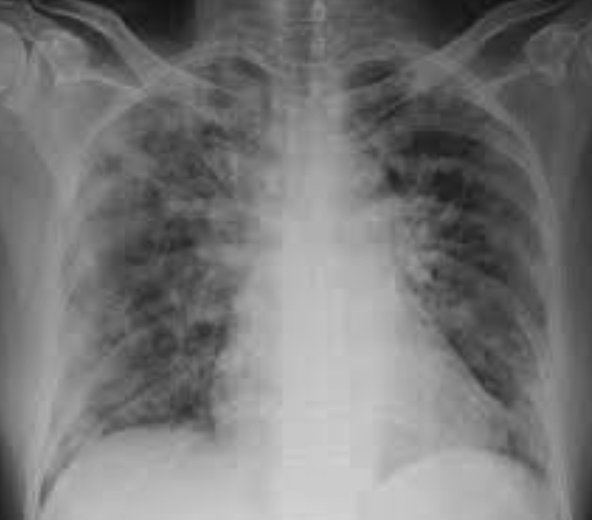

Since he had pneumonia, I pictured his lungs as a hotbed of inflammation harboring similar crusty, oozing lesions whose thick membranes and inflammatory exudate barricaded the transfer of oxygen to the bloodstream. The lungs' delicate, lace-like, elegant air sacs (alveoli) become fiery, inflamed, and thicken as they fill with fluid and pus. I’m sure you have seen pus. Think of it in your lungs.

A pathologist would report it as metaplasia (the conversion of one type of cell to another), large clots, organizing infection, heightened inflammation, cell death, and a significant reduction in the lung’s capacity to do its job. Fine, but the words crud, swamp, and devastation came to my mind. The phrase, “The pox is on(in) him,” surfaced as my patient gulped for air.

He survived, but barely. Today, as I recall his case, I picture those unfortunate COVID patients whose lungs are loaded with the same junk that barricades the transfer of lifesaving oxygen, much like my patient of years ago.

If you have vaccine hesitancy or mask resentment, I ask you to picture the blisters of adult chickenpox and the lungs of the patients on the intensive care units. Would you want lungs that looked like that? I would guess not.